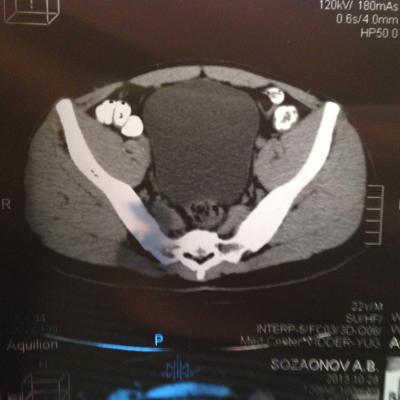

проведена МСКТ области таза!Внеорганных дополнительных патологических образований,лимфаденопатии или свободной жидкости в области таза не выявлено.

Мочевой пузырь-наполнен,стенки не утолщенны,паравезикально-без грубой органки.

Граница между предстательной железой и пузырем несколько четкая,контур пузыря на данном уровне не деформирован.

Предстательная железа-без грубой органики,еденичные микрокальцинаты.

Костно-деструктивных изменений характерных для mts со стороны костей таза не отмечено.